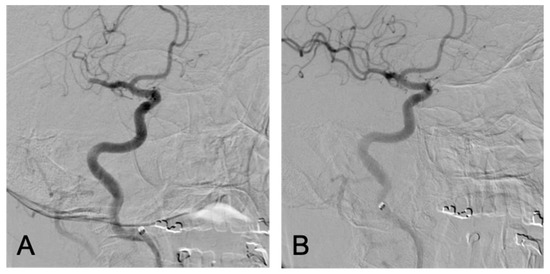

2. The Case